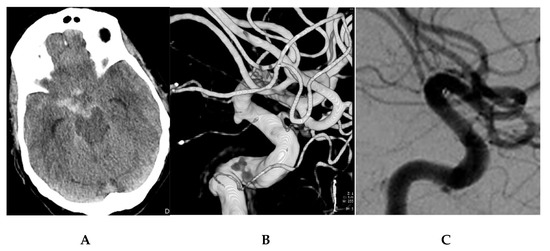

| 5–55/F (Figure 1) | 2 | 3 | Yes | L-ICA Anterolateral paraoph | A + C | 54 | 8 | PEDs 4.0 × 20 | No | C3/D | 1 | 0 |

| 12–67/F (Figure 2) | 3 | 3 | Yes | R-ICA PcomA sg | A + P | 68 | 3 | PEDs 4.00 × 16 | No | C2/D | 1 | 1 |